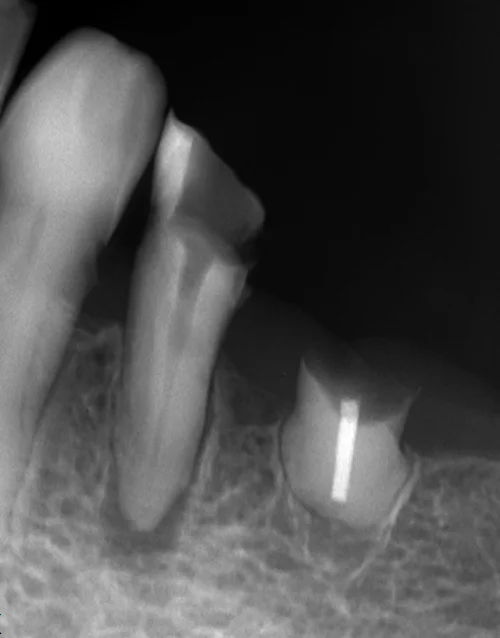

初診時のレントゲンがこちらです。